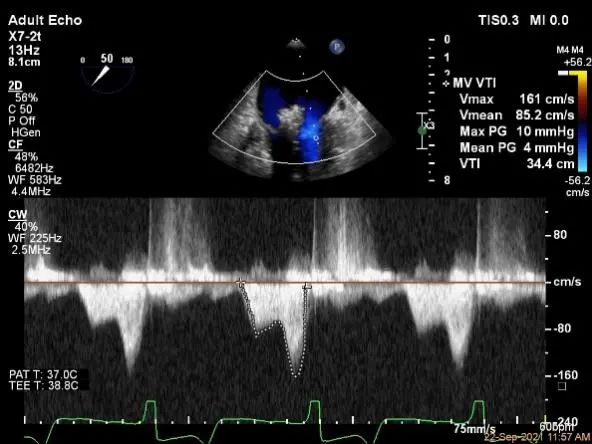

评估瓣口条件,平均跨瓣压差:2mmHg,决定在第一个夹子外侧下第二个夹子

评估瓣口条件,平均跨瓣压差:4mmHg

麻醉状态下左肺静脉血流频谱

MVA:6.67cm²